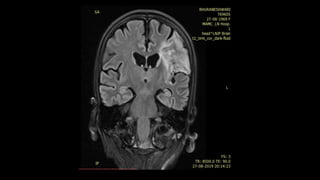

• #75 This is an example of 51y woman with sudden onset of speech difficulties and right side weakness, FAST FLAIR sequence shows left MCA cortical hyperintensity . DWI shows restricted diffusion in the corresponding areas

• #76 T2* GRE in the same case shows blooming thrombus in the left M1 segment till bifurcation. Perfusion MR shows markedly reduced cerebral blood flow in the densely ischemic core infarct which appears smaller than the corresponding DWI and FLAIR abnormality

• #77 CBV is markedly reduced in the densely ischemic core infarct (SO there is matched reduction in both CBV and CBF), however there is a penumbra of well maintained CBV . Hence there is CBV-CBF MISMATCH in this area. MTT shows prolonged transit time therefore CBV/MTT MISMATCH in the large ischemic penumbra